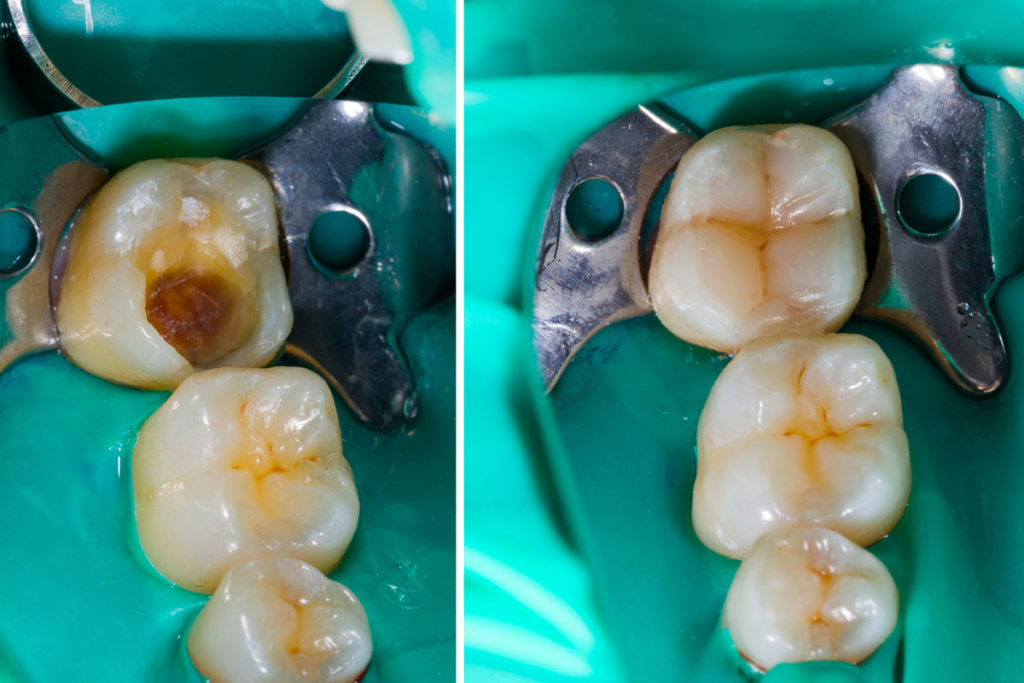

DEEP DENTAL CARIES MANAGEMENT

Indicated when the tooth pulp is infected due to deep decay, trauma, or cracks.

Modern techniques ensure safe, comfortable, and successful treatment.

Used to restore cavities, fractures, or seal post-RCT teeth.